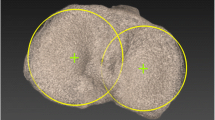

Evaluation of alignment and rotation

The femoral mechanical axis was defined as the connecting line between the centre of the femoral head and the centre of the knee. The tibial mechanical axis was the line connecting the centre of the ankle and the centre of the knee (Fig. 2). The rotational deviation of the femoral component from the referenced axis was determined by the angle between the line connecting the posterior femoral component line and the surgical epicondylar axis (Fig. 3). The tibial rotational error was defined as the angle between the angle bisecting the line of the posterior tibial component line and the transposed epicondylar axis (Fig. 4). On the basis of the spatial relationship between the femoral and tibial components and the femoral and tibial mechanical axis, the following angles were determined: the varus or valgus position of the femoral component relative to the femoral mechanical axis, the varus or valgus position of the tibial component relative to the tibial mechanical axis, the varus or valgus position of the entire limb as the sum of the tibial and femoral mechanical axes, the rotational deviation of the femoral component from the epicondylar axis and the rotational deviation of the tibial component from the epicondylar axis.

The CT scan measurement technique for the tibial rotation angle is shown. The PL line connects the posterior surface of the prosthetic posterior condyles, depicting the position of the component. The TEA is transposed to the tibial scan (TEA′) to facilitate measurement of the angle between the component and the TEA, in this patient 2 of internal rotation